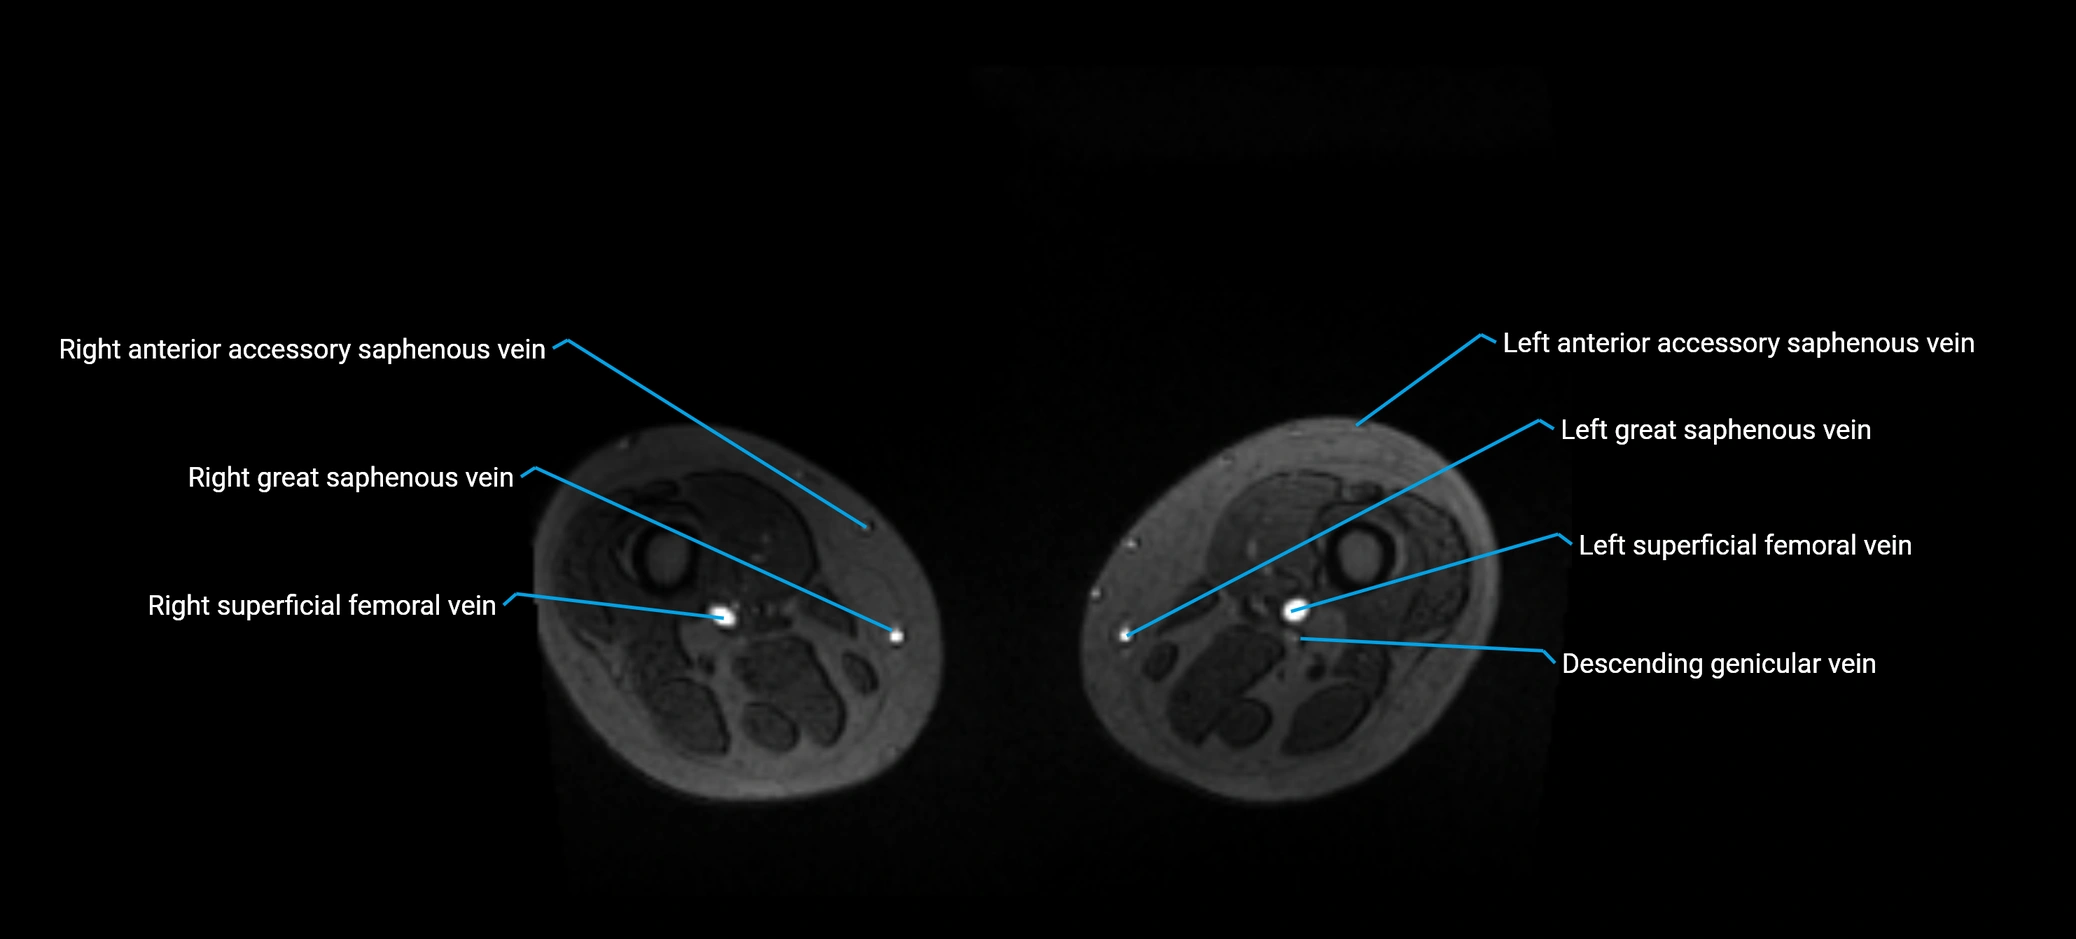

MRI image

image